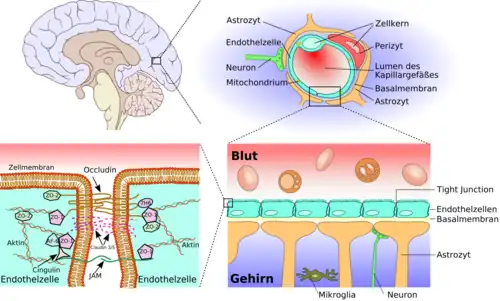

Diese besondere Abgrenzung des Bluts (intravasal) vom extravasalen Raum in Gehirn und Rückenmark ist bei allen Landwirbeltieren (Tetrapoda) ausgebildet und ermöglicht es, für das Nervengewebe eigene Milieubedingungen aufrechtzuerhalten (Homöostase). Im Wesentlichen wird diese Barriere von Endothelzellen gebildet, die hier in den kapillaren Blutgefäßen über Tight Junctions eng miteinander verknüpft sind.

Das wesentliche Element der Blut-Hirn-Schranke bilden die Endothelzellen mit ihren Tight Junctions. Für Funktion sowie Aufbau und Entwicklung der Blut-Hirn-Schranke sind jedoch noch zwei andere Zelltypen, die Perizyten und die Astrozyten, von großer Bedeutung.[1] Die Zell-Zell-Interaktionen zwischen Endothelzellen, Perizyten und Astrozyten sind so eng wie bei sonst keinen anderen Zellen. Diese drei Zelltypen zusammen bilden die Blut-Hirn-Schranke der meisten Wirbeltiere, die endotheliale Blut-Hirn-Schranke.[5][6] Die nachfolgenden anatomischen Angaben beziehen sich auf die endotheliale Blut-Hirn-Schranke der Wirbeltiere. Die bei einigen Wirbeltieren und vielen Wirbellosen ausgebildete gliale Blut-Hirn-Schranke wird am Ende dieses Kapitels gesondert aufgeführt.

Das Endothel

Die Kapillargefäße werden – wie in den peripheren Blutgefäßen auch – von Endothelzellen gebildet. Das Endothel peripherer Kapillaren hat, für den Austausch von Wasser und darin gelösten oder suspendierten Stoffen zwischen dem Blut und der extrazellulären Flüssigkeit des umliegenden Gewebes, Öffnungen (Fenestrierungen) von ca. 50 nm Durchmesser und Zwischenzellspalten von 0,1 bis 1 µm Weite. Zwischen den Endothelzellen im Gehirn gibt es dagegen keine Fenestrierungen und keine Intrazellularspalten,[7] weshalb man auch von einem kontinuierlichen Endothel spricht.[8] Die dem Innenraum der Kapillare zugewandte (luminale) Membran unterscheidet sich bezüglich der Art der Membranproteine erheblich von der dem Interstitium zugewandten apikalen Seite.

Die Endothelzellen sind über feste Zell-Zell-Verbindungen, die sogenannten Tight Junctions, miteinander verbunden. Diese Tight Junctions stellen dichte Verbindungen zwischen benachbarten Zellen dar und liefern einen wesentlichen Beitrag für die Schrankenfunktion der Blut-Hirn-Schranke.[24][25] Denn sie dichten den Raum zwischen den Zellen ab und schließen so einen parazellulären Transport, die Passage von Stoffen längs des interzellulären Spaltraums zwischen benachbarten Endothelzellen an diesen vorbei, praktisch aus.[26][27][28]

Die Basallamina

Die Endothelzellen sind von einer Proteinschicht, der Basallamina, vollständig umgeben.[8] Diese Doppelschicht ist ungefähr 40 bis 50 nm stark und nur im Elektronenmikroskop sichtbar. Sie besteht im Wesentlichen aus dem Kollagen Typ IV, Heparinsulfat-Proteoglykanen, Laminin, Fibronektin und anderen extrazellulären Matrixproteinen. Die Basallamina grenzt an die Plasmamembran der Endfüßchen der Astrozyten.[10][26]

Die Perizyten

Die Astrozyten

Astrozyten sind sternförmig verzweigte, im Vergleich zu den Perizyten deutlich größere Zellen aus der Familie der Makroglia. Sie werden dem Zentralen Nervensystem zugerechnet und sind nach der Geburt noch teilungsfähig. Bei höheren Wirbeltieren haben sie keine direkte Schrankenfunktion, auch wenn sie die Kapillargefäße im Gehirn zu etwa 99 % mit ihren Endfüßchen bedecken.[6][53] Sie stehen allerdings in unmittelbarer Wechselwirkung mit den Endothelien.[54] Astrozyten induzieren in den Endothelien der zerebralen Blutgefäße die Funktion der Blut-Hirn-Schranke. Dies wurde durch Transplantationsversuche nachgewiesen. Zerebrale Blutgefäße, die in periphere Organe verpflanzt wurden, verhielten sich wie die dort vorhandenen „normalen“ Kapillaren und bildeten beispielsweise Fenestrierungen aus. Im umgekehrten Versuch nahmen periphere Kapillaren, die in das Zentralnervensystem verpflanzt wurden, den dortigen Phänotyp mit Tight Junctions an.[1][55] Auch in In-vitro-Versuchen zeigt sich der Einfluss der Astrozyten auf die Phänotypausprägung der Endothelien. In Co-Kulturen aus Astrozyten und Endothelzellen weisen die Endothelien eine höhere Dichtigkeit auf als in reinen Endothelkulturen.[56]